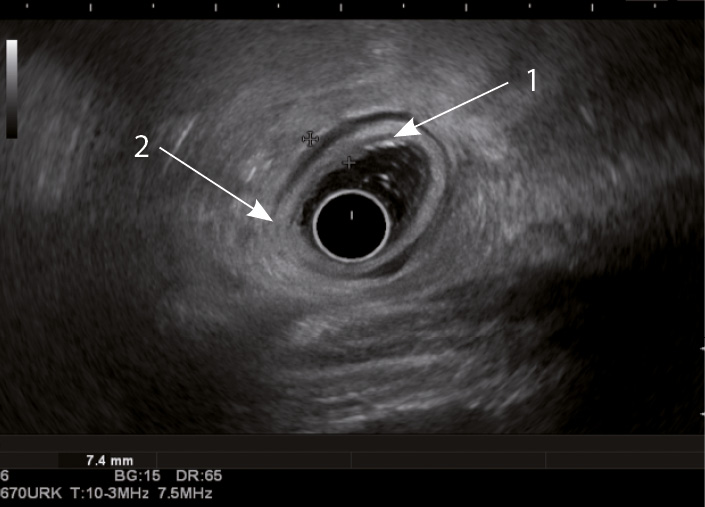

Рис. 4. Эндосонографическая картина толстой кишки при болезни Крона; 1 – отсутствие дифференцировки слоев кишечной стенки; 2 – утолщение стенки толстой кишки за счет всех слоев

Кишечная стенка статистически значимо чаще утолщалась за счет слизисто-подслизистого слоя при ЯК, чем при БК: в 82 и 7,14% соответственно; диагностическая чувствительность данного признака была 82%, а специфичность – 93% (табл. 1). При БК изменение стенки толстой кишки за счет трансмурального утолщения выявлялось статистически значимо чаще (68%), чем при ЯК (9%) (чувствительность 68%, специфичность 91%). Статистически значимых различий в частоте изменений мышечного слоя кишки отмечено не было. Только при БК в 68% случаев отсутствовала дифференцировка слоев кишечной стенки в фазе обострения (чувствительность и специфичность признака составили 68 и 100% соответственно) (см. рис. 4). При ЯК на фоне «смазанности» слизисто-подслизистого слоя у всех больных можно было визуализировать мышечный и серозный слои (см. табл. 1, рис. 3).